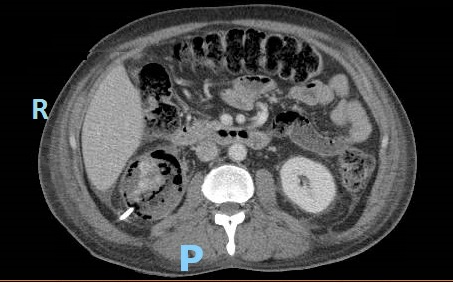

Case Presentation: A 50 year old man with poorly controlled type 2 diabetes mellitus (DM) presented with flank pain, nausea, vomiting, and fever. On exam, he was febrile, tachycardic, hypotensive, and had right sided CVA tenderness. The ER performed a CT stone protocol, however, imaging demonstrated right sided emphysematous pyelonephritis (EPN). Our patient was admitted with severe sepsis, pre-renal acute kidney injury, hyponatremia, and hyperglycemia. Piperacillin/Tazobactam was started, appropriate IV fluid resuscitation was administered, and urology was consulted. Urology recommended placement of both a Foley catheter and percutaneous nephrostomy tube for maximal drainage, even though there were no signs of obstruction. Interim lab work demonstrated a hemoglobin A1c of 16%, increased from 12%. Three days later, despite stable blood pressures and blood and urine cultures demonstrating antibiotic sensitive E. coli, he continued to have a rising leukocytosis, tachycardia, and severe pain. Repeat CT abdomen/pelvis with contrast showed new areas of necrosis and new abscesses in the anterior and lower pole of the right kidney and retroperitoneum. He was taken to the OR for emergent nephrectomy. His course was further complicated by IVC injury and hemorrhagic shock requiring massive transfusion. Subsequent anasarca precluded closure of his abdominal incision and he was monitored in the SICU. He returned to the OR six days later for closure and was discharged home after receiving insulin teaching and DM education.

Discussion: This case highlights the importance of diabetes management in prevention of EPN. Over 80% of patients with EPN have concurrent DM. Our patient’s only risk factor was DM; he had no evidence of obstructive uropathy, was not over age 60, and was not of female sex. Hyperglycemia and glucosuria provide favorable conditions for gas forming pathogens to cause severe infection. DM related autonomic neuropathy results in incomplete emptying of the bladder, further increasing the risk of ascending urinary tract infection. In vitro studies also demonstrate that humoral immunity and neutrophil function are impaired in diabetic patients. This is likely why our patient did not appear clinically worse despite the formation of new abscesses.Management of EPN consists of antibiotic administration and drainage by percutaneous nephrostomy. If these measures are insufficient, total nephrectomy is necessary. CT scan provides prompt diagnosis and staging so appropriate treatment is initiated to preserve renal function and prevent clinical deterioration. CT should be repeated within 3 days if there is concern for worsening infection. Although cases of EPN are fairly rare, its strong association with DM supports the need for optimal glycemic control in our diabetic patients. Additionally, a lower threshold for repeat imaging and escalation of care is warranted in these patients due to their impaired inflammatory response.